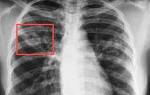

4. Туберкулема рентгенологически представляет собой округлое образование 2-5смв диаметре с четкими границами, располагающееся в 1-2 сегменте чаще справа. Это исход инфильтративного туберкулеза, когда перифокальное воспаление рассасывается и остается очаг творожистого некроза, окруженный капсулой.

• Топическая лучевая диагностика. Основным методом диагностики туберкулеза является рентгенография легких. При этом можно обнаружить очаги инфекции, как в легких, так и в других органах и тканях. При необходимости выполняют КТ легких.